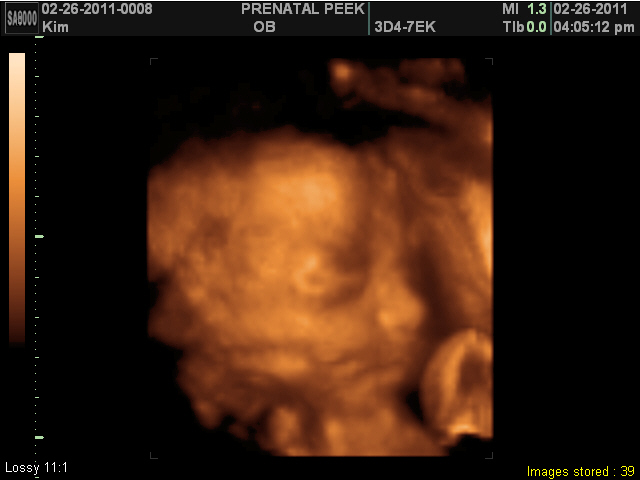

3D Sonogram!!